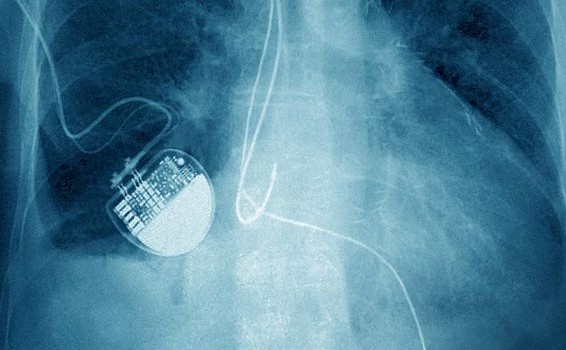

Közel fél millió szívritmus szabályozó viselője válhat a hekkerek áldozatává!

A hír tényleg rémületes: az FDA 465.000 pacemaker visszahívását engedélyezte a hekkelés potenciális veszélyének elhárítására. (tovább…)